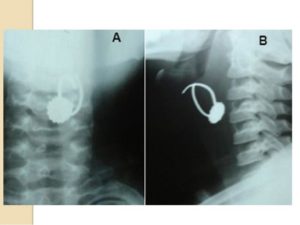

Для установления конкретного местонахождения предмета также могут проводить рентгенографическое исследование.

Специализированную помощь оказывают оториноларингологи совместно с эндоскопистами. Для этого проводят непрямую ларингоскопию, рентгенологическое исследование шейного отдела в двух проекциях (по Г.М.Земцову), позволяющее обнаружить тень инородного тела, косвенные признаки неконтрастного инородного тела пищевода или повреждения его стенок.